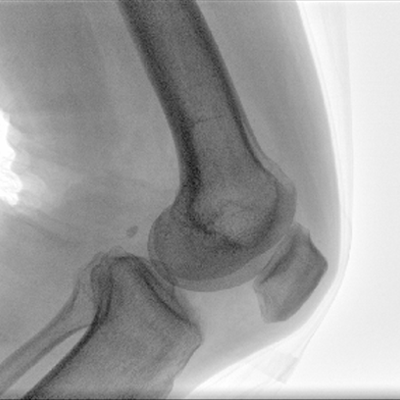

Clinical picture

臨床圖片